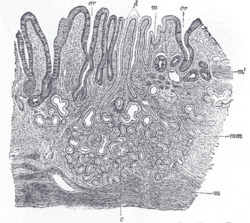

![]() Cardiac glands shown at c and their ducts at d | |

The cardiac glands are found in the cardia of the stomach which is the part nearest to the heart, enclosing the opening where the esophagus joins to the stomach. Only cardiac glands are found here and they primarily secrete mucus.[4] They are fewer in number than the other gastric glands and are more shallowly positioned in the mucosa. There are two kinds - either simple tubular with short ducts or compound racemose resembling the duodenal Brunner's glands.

Human cardiac glands (at cardia)

Human pyloric glands (at pylorus)

Human fundic glands (at fundus)